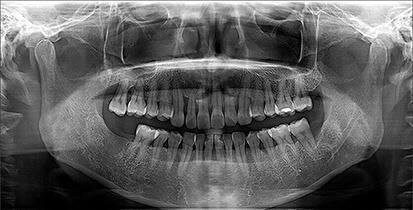

جراحة الأسنان هي إجراءات طبية تُجرى داخل الفم لعلاج مشاكل في الأسنان أو اللثة أو الفك أو الأنسجة المحيطة بها.

غالبًا تتم الجراحة تحت تخدير موضعي، وقد تكون بسيطة أو معقّدة حسب الحالة.

متى أحتاج لجراحة أسنان؟

قد يقترح الطبيب الجراحة إذا كان لديك:

- سن مكسور أو مدفون داخل العظم

- خراج أو التهاب متكرر

- ألم من ضرس العقل

- أمراض لثة متقدمة

- سن مفقود وتحتاج إلى زراعة

- مشاكل في عظام الفك